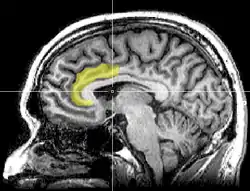

Envy and schadenfreude are related emotions. Takahashi, et al. (2009) looked at the areas of the brain that were active when feelings of envy and schadenfreude were evoked. Using functional magnetic resonance imaging (fMRI) researchers looked for activity in the dorsal anterior cingulate cortex (dACC) (seen in image 2.) when envy was felt, as the anterior cingulate cortex is the area that is activated when our positive self-concept is being conflicted with external information, social pain, or cognitive conflicts (Takahashi, et al., 2009). When investigating the emotion of schadenfreude they were looking for activation in the ventral striatum, which is the central node of the rewards processing area (Takahashi, et al., 2009). The reward would be the joy that is derived in schadenfreude. Takahashi, et al. (2009) found that both areas which were targeted in their respective trials activated when the respective emotion was emitted. They found that when people had higher levels of schadenfreude, greater activation was seen in the ventral striatum. This was also found to be the case when investigating envy. Greater levels of envy showed higher activation in the dACC (Takahashi, et al., 2009).